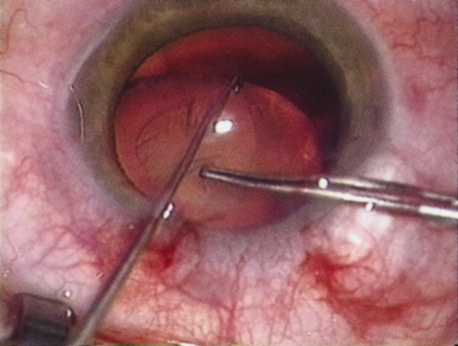

Retrobulbar blocks were among the earliest of orbital block techniques and have stood the test of time. Although there are many approaches to block administration, each technique intends delivery of the anesthetic medication into the intraconal space. These blocks are highly effective (about 95%) in achieving adequate ocular akinesia and anesthesia. Potential complications include retrobulbar hemorrhage,67 globe penetration,68,69 optic nerve sheath hemorrhage, extraocular muscle toxicity with persistent diplopia, and, rarely, brainstem anesthesia. Visualization of the globe is improved when using a transconjunctival approach (Fig. 6) or when the skin is indented with a cotton-tipped applicator (Fig. 7), making globe perforation less likely.

Fig. 7. The skin is indented with a sterile cotton-tipped applicator until it is past the equator of the globe, thereby reducing the risk of globe perforation when the needle is inserted.